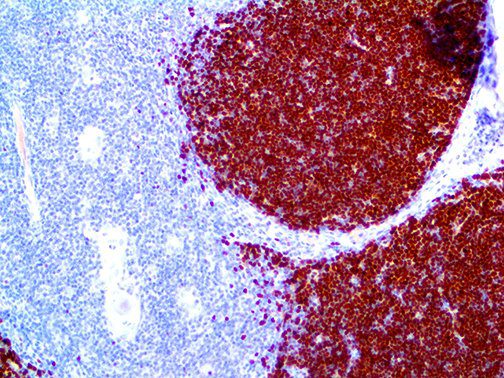

It is the ICU physician who is most likely to witness one of the deadliest manifestations of the abnormal immunological response, the cytokine storm syndrome (CSS). This response is also referred to by some as the cytokine release syndrome (CRS). CSS is characterized by continuous activation and expansion of macrophage and lymphocyte populations, which secrete large amounts of cytokines, causing the cytokine storm. This massive cytokine release is akin to hemophagocytic lymphohistiocytosis (HLH) disease, a syndrome characterized by initial unchecked and persistent activation of cytotoxic T lymphocytes and NK cells.

Clinical and laboratory manifestations of HLH include fever, enlarged liver and/or spleen, neurologic dysfunction, coagulopathy, liver dysfunction, cytopenias (i.e., low levels of erythrocytes, leukocytes, and/or platelets), hypertriglyceridemia, hyperferritinemia, hemophagocytosis, and eventually diminished NK cell activity as the immune system becomes progressively paralyzed. HLH can be familial (primary HLH) or secondary to another disease process (sHLH), such as rheumatic disease, in which it is referred to as macrophage activation syndrome (MAS, characterized by elevated ferritin).